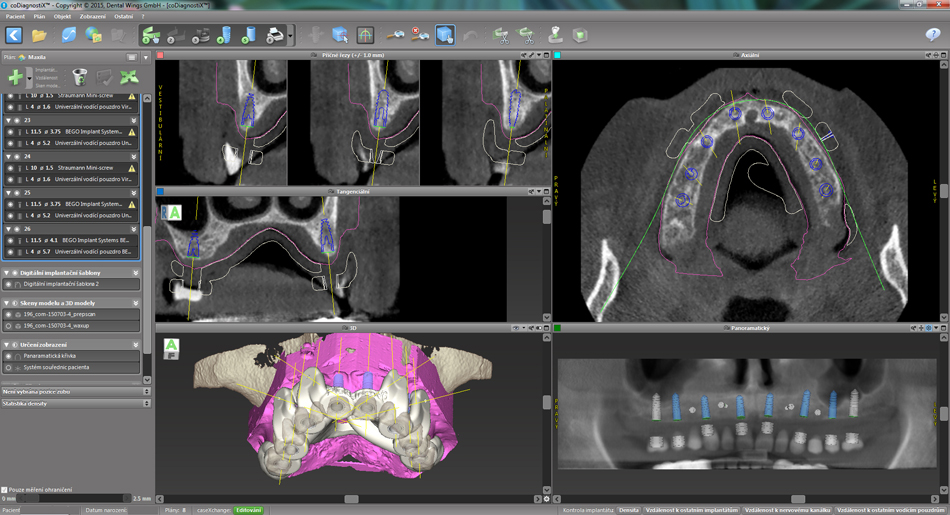

Chirurgicko-protetický plán vychází z 3D rentgenu čelisti, otisku zubů a dásně (scanu zubů a dásně) a finálního návrhu protetické náhrady. Na základě těchto dat je v plánovacím softwaru coDiagnostiX vytvořena chirurgická šablona,

která je následně vytištěna na 3D tiskárně a použitá v den výkonu. Od roku 2014 jsme tuto metodu jako první v ČR začali využívat a nadále se podílíme na vývoji a vylepšování chirurgických šablon pro ještě přesnější a předvídatelnější výsledky.

Jedná se o externí plánovací program, spojený se zubní laboratoří a frézovacím centrem, který využívá dat získaných z 3D rentgenu čelisti, otisku zubů a dásně (scanu zubů a dásně) a finálního návrhu protetické náhrady.

Tento program umožňuje tříprostorovou počítačovou simulaci při plánování pozic implantátů. Součástí programu je i databáze, ve které mohou být uloženy všechny typy implantátů od všech výrobců, včetně jejich délek, průměrů i tvarů.

Lékař si vytvoří všechny typy zobrazení potřebných pro naplánování – tedy 2D snímky (panoramatický), příčné řezy i 3D model.

Vidí zde i důležité anatomické útvary – čelistní dutinu, průběh nervu atd. Po proměření množství kosti – šířky i výšky vybere z databáze vhodný typ implantátu a umístí ho do požadované lokality. Ihned vidí jeho pozici ve všech 3 rovinách

a na všech snímcích i 3D modelu. Může upravovat podle potřeby jeho pozici, sklon atd.

Všechny vybrané a správně umístěné simulované implantáty se ukládají do „počítačové karty“ pacienta s jejich pozicí, délkou, průměrem, typem i sklonem. V programu také lékař navrhuje chirurgické šablony pro řízenou nebo navigovanou implantaci.

Lékař i pacient tedy ještě před vlastní operací vidí, jak by mělo ošetření probíhat a vypadat.